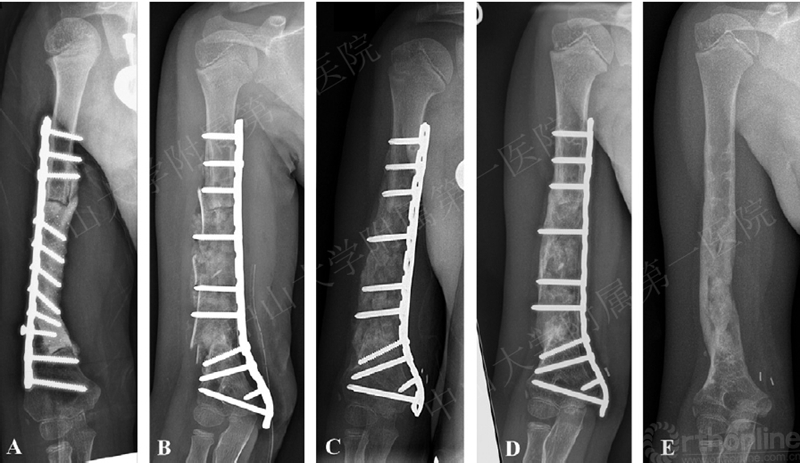

病例分享:7岁肱骨中下段尤文肉瘤患者。

A第1阶段术后X线 B第2阶段术后X线 C第2阶段术后45天 D术后5个月 E术后1年